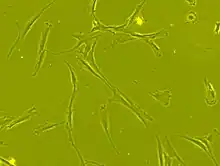

Stem cell transplantation is an important avenue for SCI research: the goal is to replace lost spinal cord cells, allow reconnection in broken neural circuits by regrowing axons, and to create an environment in the tissues that is favorable to growth.[76] A key avenue of SCI research is research on stem cells, which can differentiate into other types of cells—including those lost after SCI.[76] Types of cells being researched for use in SCI include embryonic stem cells, neural stem cells, mesenchymal stem cells, olfactory ensheathing cells, Schwann cells, activated macrophages, and induced pluripotent stem cells.[162] Hundreds of stem cell studies have been done in humans, with promising but inconclusive results.[149] An ongoing Phase 2 trial in 2016 presented data[163] showing that after 90 days, 2 out of 4 subjects had already improved two motor levels and had thus already achieved its endpoint of 2/5 patients improving two levels within 6–12 months. Six-month data is expected in January 2017.[164]